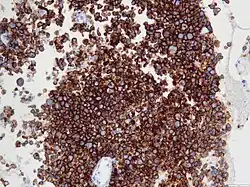

Micrograph of an anaplastic large-cell lymphoma. H&E stain. | |